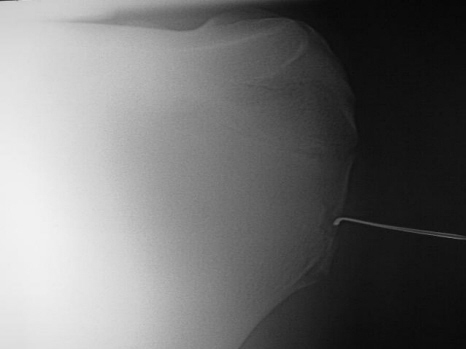

Fraktur Schulter